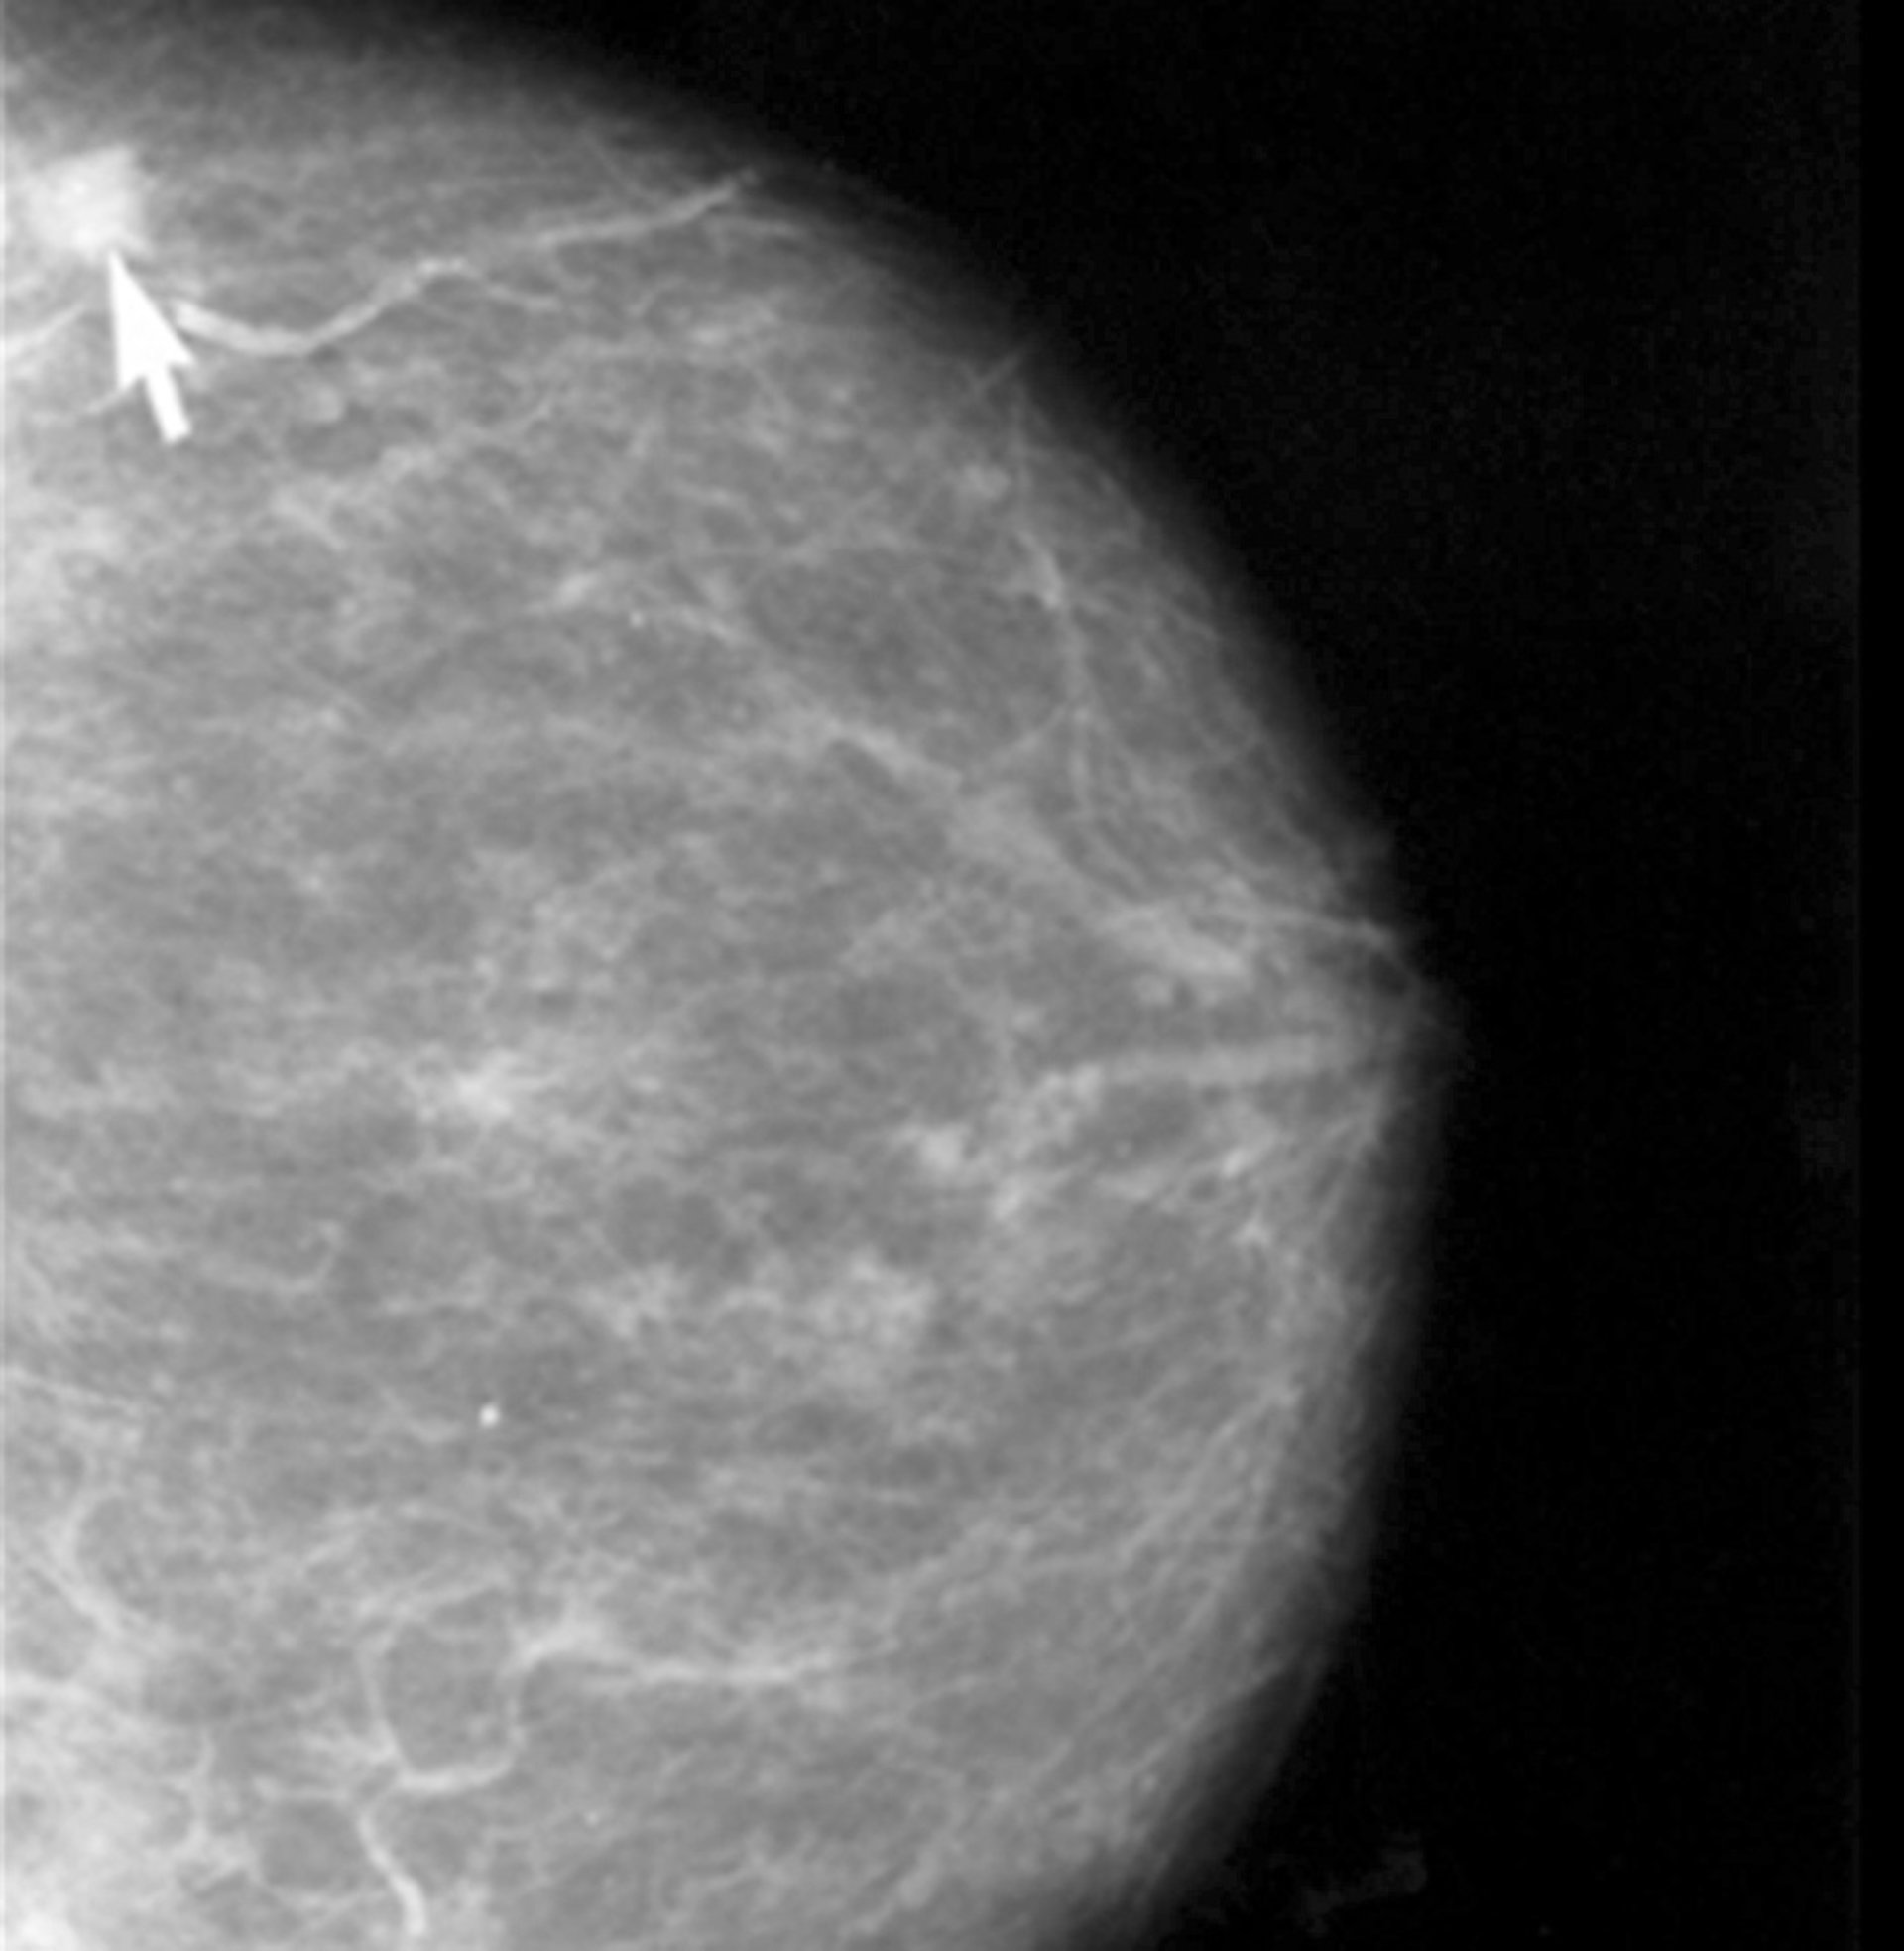

Investigan la quimiorresistencia en el cáncer de mama

Cáncer de Mama